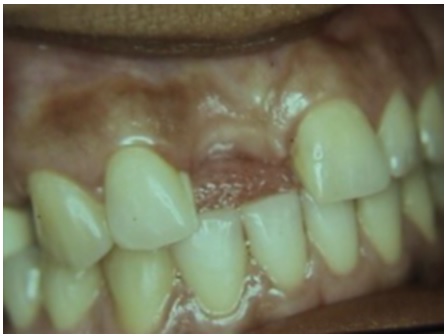

Se presentó a la consulta una mujer de 35 años de edad, sin antecedentes médicos relevantes, quien fue remitida por el rehabilitador oral para corregir una atrofia del reborde alveolar tipo I moderada en la zona del diente 11 (nomenclatura dígito 2). El tratamiento incluía realizar un puente Maryland, prótesis fija adhesiva que se sujetaría en la superficie interna de los dientes, para evitar preparar los dientes pilares o de soporte, pues la paciente descartó la colocación de un implante o la preparación de los dientes adyacentes (figura 1).

El defecto que presentaba la paciente requirió aumento del grosor más no de la altura del reborde alveolar, por lo que se decidió realizar una técnica de bolsillo (22). El procedimiento quirúrgico consistió en la preparación del receptor mediante una incisión horizontal paracrestal palatina de la zona mesial del 12 a la zona mesial de 21, incluyendo la papila interdental, con incisiones relajantes hechas en ángulo en mesial del 21 y el 12, y elevación de un colgajo mucoso. Luego se tomó un injerto conectivo sin collar de epitelio del sitio donante palatino derecho. Para esto, se realizó una incisión horizontal a 2 mm del margen gingival palatino de mesial del 16 a distal del 13; se elevó la tapa epitelial palatina sin incisiones relajantes. El objetivo de los cortes era poder tomar el injerto de tejido conectivo, los cuales son un corte horizontal interno apical y dos cortes verticales internos mesial y distal. Se procedió a tomar el injerto de tejido conectivo sin collar de epitelio, el cual se dejó dentro del sitio receptor mientras se realizó la sutura del sitio donante palatino (figura 2).